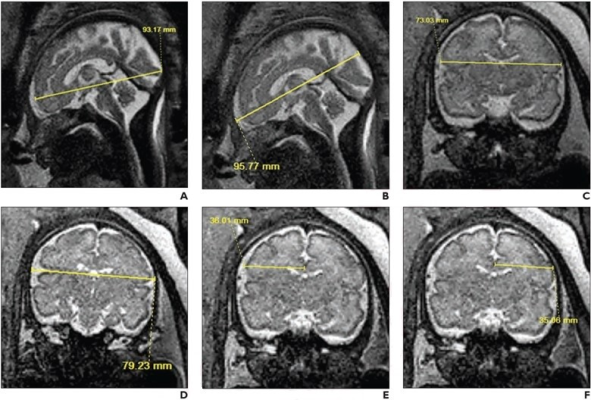

Пациентка 33 лет (гестационный возраст 30 недель и 6 дней), без внутриутробного воздействия опиоидов, которой была проведена МРТ плода. Сагиттальные (A, B) и коронарные (CF) T2-взвешенные изображения SSFSE показывают двумерные измерения лобно-затылочного диаметра головного мозга (A), лобно-затылочного диаметра кости (B), бипариетального диаметра мозга (C), бипариетального диаметра кости (D ), правый мозговой бипариетальный диаметр (Е), левый мозговой бипариетальный диаметр (F).

При поправке на гестационный возраст, пол плода и воздействие никотина 7 из 14 двухмерных биометрических измерений — лобно-затылочный диаметр головного мозга, бипариетальный диаметр кости, бипариетальный диаметр головного мозга, длина мозолистого тела, высота червя, передне-заднее измерение моста и поперечное диаметр мозжечка – были значительно меньше у плодов, подвергшихся воздействию опиоидов, чем у плодов, не подвергавшихся воздействию, по данным МРТ плода.